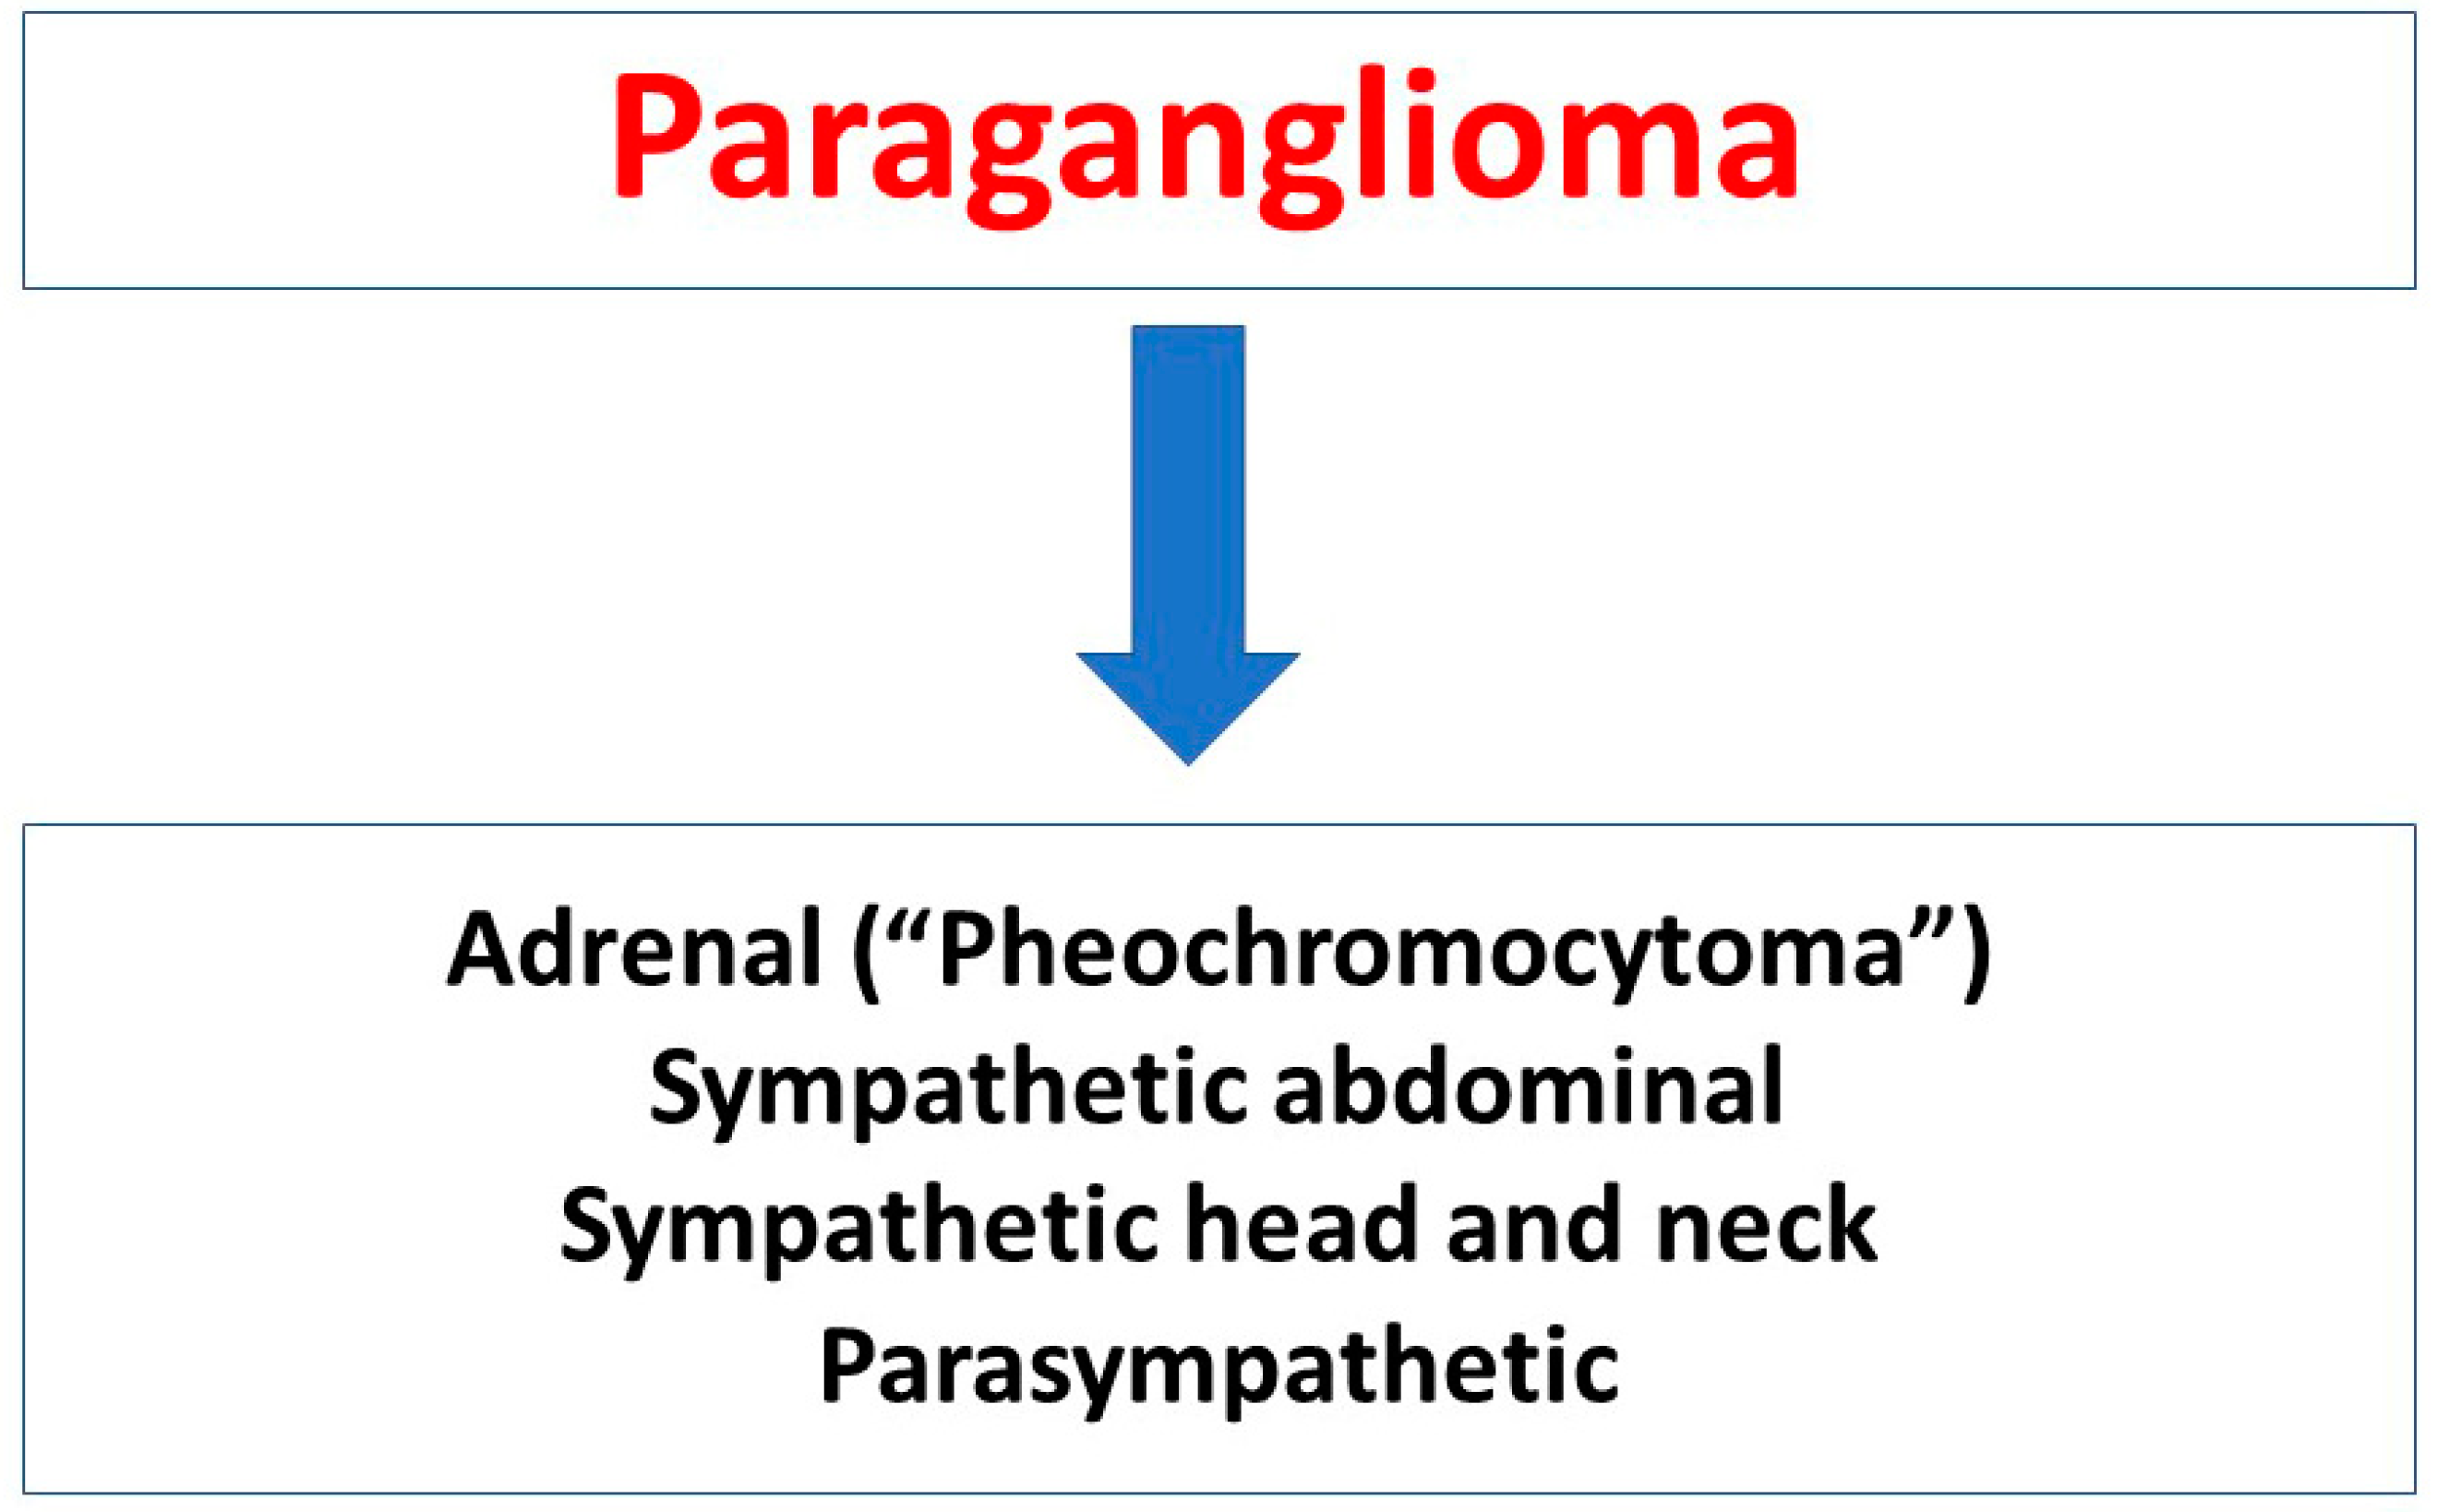

3. Pheochromocytomas and Paragangliomas According to World Health Organization and American Joint Committee on Cancer Classifications

3.1. WHO Classification

3.2. AJCC Classification